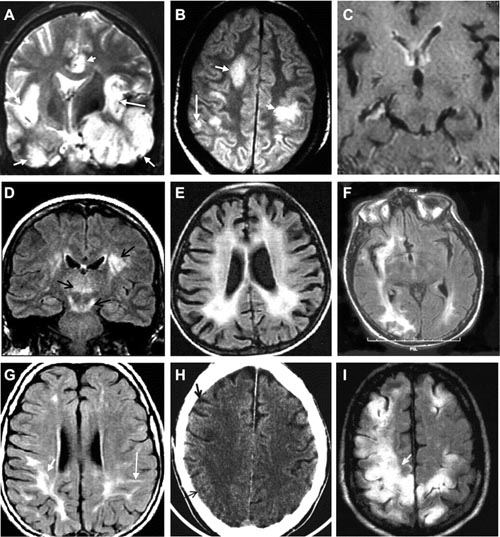

Hình ảnh học

Thực hiện đầu tiên khi nghi ngờ viêm não.

Cung cấp thông tin đánh giá nhiễm trùng hệ thần kinh TW nhưng thường không đặc hiệu. Phát hiện sau khởi phát triệu chứng 2-4 ngày.

MRI nhạy hơn CT trong việc phát hiện sớm những sang thương trên não do HSE (Neurologist 2000;6:145–59.)

Tổn thương gợi ý chẩn đoán: T1 giảm và T2 tăng ở chất xám thuỳ thái dương trong và thuỳ trán ổ mắt, có thể có xuất huyết kèm theo, thường không đối xứng. Ngoài ra tổn thương có thể lan đến thuỳ đảo và hồi góc, có thể bắt Gado màng não và các hồi não.

MRI bình thường trong khoảng 10% BN HSV-PCR (+). Nhưng số còn lại đều có tổn thương thuỳ thái dương (90%)